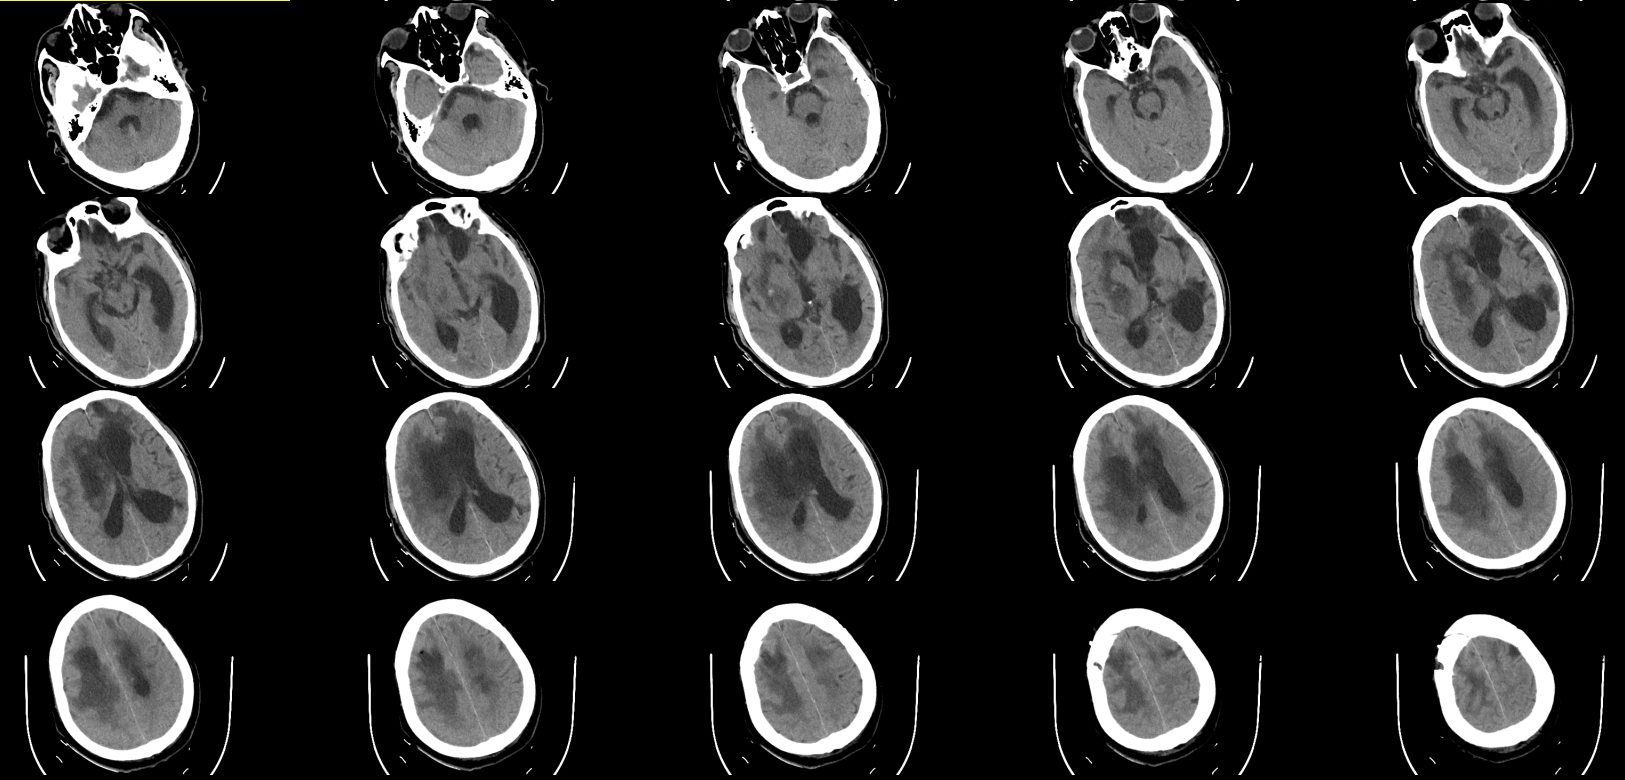

术前CT